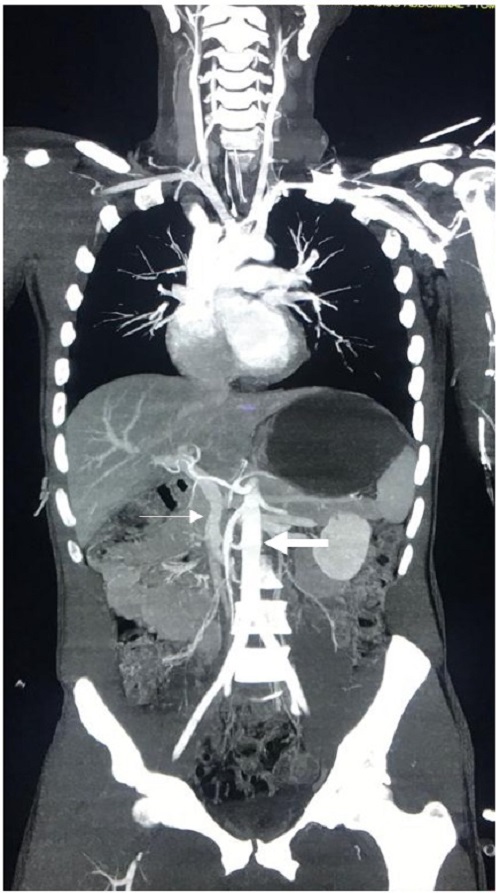

The result is both a venous and arterial phase in a single high-resolution image (Figure 1). From January 2017 to December 2018, an observational, prospective study was performed at our Level I Trauma Center where we tabulated a total of 263 severely injured trauma patients who underwent whole body computed tomography as part of their initial evaluation. One hundred and sixty-eight had blunt trauma and were hemodynamically stable (Group 1), 50 patients had blunt trauma and were hemodynamically unstable (Group 2) and 45 had penetrating trauma with or without hemodynamic instability (Group 3). Median injury severity score was 22 (IQR= 16-22) and 172 (65.4%) patients received non-operative management, without significant differences between groups. Median time between emergency department and whole body computed tomography was 28 minutes (IQR= 14-5) and the median radiation dose was less than 20 mSv, which is considered to be the optimal range of exposure that does not increase significantly long-term cancer risks 23-25. Ninety-one (34%) patients required surgical management, without significant differences among groups [Group 1: 59 (35.1%); Group 2: 15 (30%); Group 3: 17 (37.7%); p= 0.23]. All patients who required surgery had positive findings during their procedure 26. These results provide supporting evidence towards our claims that whole body computed tomography is a safe, effective and efficient tool in the initial workup and subsequent management of the severely injured trauma patient regardless of their hemodynamic status. Furthermore, it could potentially avoid unnecessary procedures in patients that could be managed otherwise non-operatively, decreasing overall costs and morbidity in these patients.